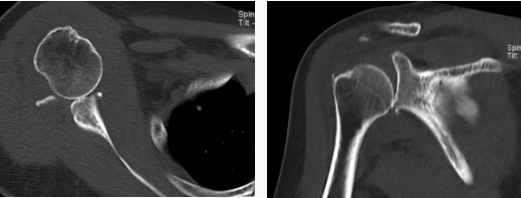

病例2

病史摘要:女性,65歲,跌傷致右肩活動受限9天。

CT圖示:右側(cè)肱骨頭后上部局部明顯凹陷,局部骨皮質(zhì)欠光整(箭頭),外緣見小片狀骨碎片影;右側(cè)肱骨頭向下方移位,關(guān)節(jié)間隙增寬;前下盂唇骨質(zhì)不連續(xù),見多發(fā)小碎骨片影并游離(三角形)。